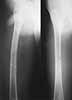

We managed to get neutral phosphate, initiated medical treatment and did an antegrade SIGN nailing of left femur along with couple of screws to neck using miss a nail technique. He complained of pain of the right femur and both forearms. In OT these areas were screened using image intensifier and found that he has looser zones of all these with impending fractures. Yesterday we did a retrograde nailing of right femur usingSIGN nail. Both ulnas were stabilised usingLambrudini wires in a closed fashion. All fractures and looser zones were stabilised by closed surgery using image intensifier. It may be interesting to see the post of picture of both the hips in which one side shows an antegrade femoral SIGN nail and the other side shows a retrograde SIGN nail.